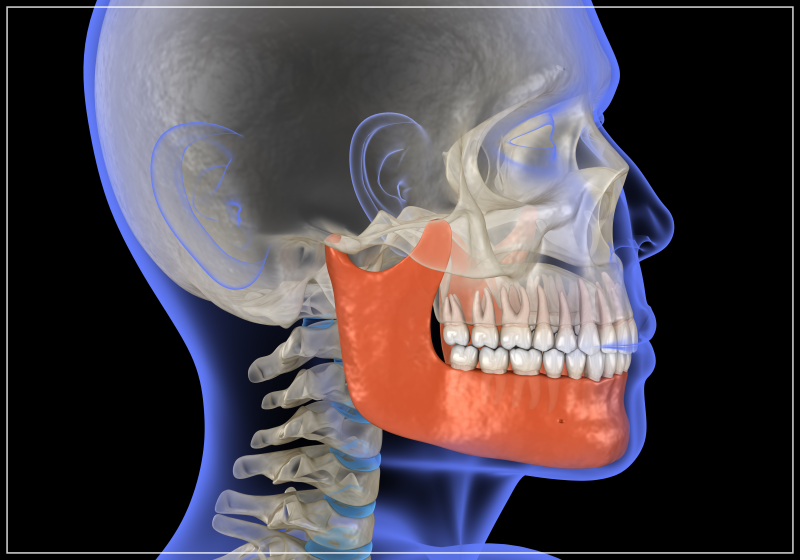

트랙션방식이란 무엇인가요?

트랙션 방식의 원리부터 먼저 설명드리자면

위 아래턱을 당기는 악간 견인을 통해서

대체 디스크를 두껍게 형성함으로써

상실된 관절의 높이를 회복시키는

과정으로 이루어지는데요.

이러한 트랙션 방식은 일반적인

턱관절 장치와는 달리 교정없이

치아의 교합을 효과적으로 개선하고

개방교합을 해결할 수 있다는

장점이 있지만,